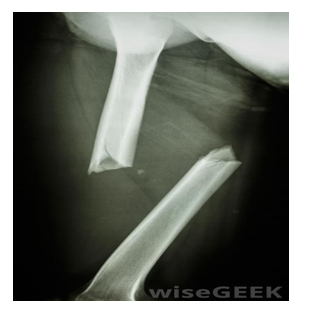

This is the oldest and most common diagnostic imaging technique.3 It is a non-invasive technique like the ultrasonography, however it uses a very small amount of ionizing or non-ionizing radiation (X-rays) generated by an X-ray machine to produce a latent image of internal structures of the body on an X-ray film (Projectional radiography). An X-ray machine can be fixed, mobile or portable (Figure 17–19).48–51 During radiography, the X-rays is directed to the body allowing it to pass through the target organ and then captured behind the flat X-ray film to produce a 2D image (Figure 20). X-ray examination can be done with or without a contrast media (such as barium or iodine) depending on the density of the organ to be examined. Radiography can be used in diagnosing several conditions such as bone fracture and cancer, breast tumor and tuberculosis.48 There are some risks associated with excess exposure to X-ray such as cancer, hair loss and skin burns. But in most cases the benefits outweigh the risks.3,52

Figure 20 A radiograph of a mid-humeral fracture.3